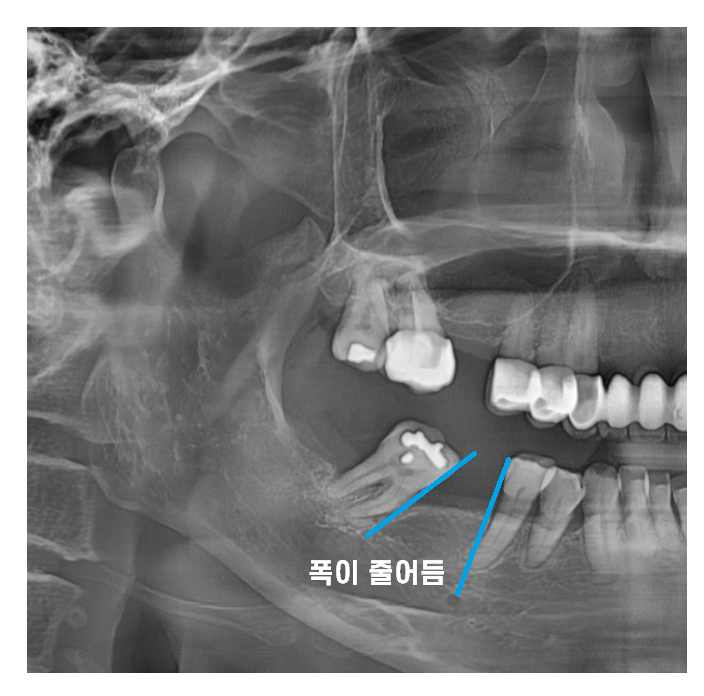

치아가 빠지게 되면 다른 치아들이

빈 공간으로 이동하면서 배열이 엉킬 수 있습니다.

오늘 환자분도 빠진 어금니 방치하다가

멀쩡한 큰 어금니가 많이 기울어졌습니다.

뿌리가 이동을 하기에

겉으로 보기에는 많이 쓰러졌는지

모르는게 문제입니다.

x-ray를 찍어보면

치아가 기울어진게 보이는데 말이죠

빠진 어금니 방치하다가

치아가 쓰러져

해당 환자분은 임플란트를 심을 공간이

부족하셨습니다.

공간이 좁아지면 임플란트를 심더라도

음식물이 끼고 불편하고

공간이 안나오면

옆 치아도 치료해야하고